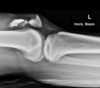

43 F presents with L knee pain and effusion from 'twisting' her knee Diagnosis?

lipohemarthrosis. results from an intra-articular fracture with escape of fat and blood from the bone marrow into the joint, and is most frequently seen in the knee, associated with a tibial plateau fracture or distal femoral fracture; rarely a patellar fracture XR Subtle tri-layer appearance due to fat on serum on red cells.